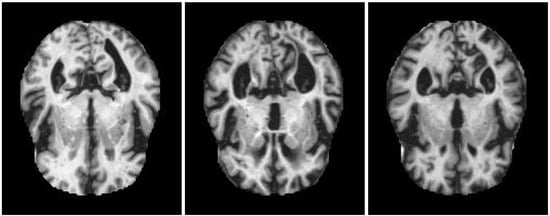

Some examples of the three classes are shown in Figure 2. At first sight, the images belonging to different classes are much the same in both color and shape, and their dissimilarities appear slight. Nonetheless, an expert clinician can spot the areas containing differences and, hence, assign the images to the different classes.

As a first pro, it should be observed that images belonging to different classes are actually quite alike, as Figure 2 has shown. Adding to this, the colors of the images from diverse classes are practically equal. Hence, our approach cannot rely on differences in colors or shapes when assigning the items to the classes. With regards to this, these experiments show a worst-case situation. Nonetheless, this does not impact results.

Figure 2. Example of items from the three classes. Left pane: non-demented. Center pane: mild demented. Right pane: moderate demented. MRI images contained in this figure are taken from the original Alzheimer’s data set [53] available on Kaggle.